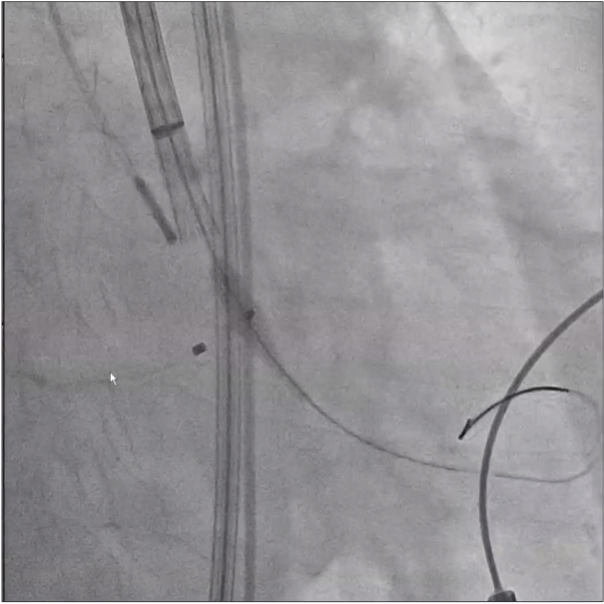

首先进行球囊预扩、造影,判断左右冠开口情况,实际显示冠脉灌注良好,将根据瓣膜植入后情况再决定是否进行冠脉干预,由于患者血管入路短径小于5.5mm,使用大鞘将难以通过并造成血管损伤,采用内联鞘直接进入递送系统,超强的顺应性使得递送顺利过弓和跨瓣。

在CUSP OVERLAP投照角度下进行瓣膜释放,释放过程中杨毅宁教授密切关注患者各项体征指标以及各器材位置情况,稳步操作最终达到预计位置精准定位,术后跨瓣压差即刻降低至0,患者双侧冠脉灌注良好,无反流,超声检测血流动力学明显改善,手术取得圆满成功。 中心简介 新疆维吾尔自治区人民医院始建于1934年,是一所集医疗、教学、科研、预防、保健和社区卫生服务为一体的大型综合性“三级甲等医院”。曾先后荣获“全国文明单位”、“全国百佳医院”、“全国五·一劳动奖状”、“全国卫生系统先进集体”、“全国万名医师支援农村卫生工程先进集体”、“全国十大百姓放心医院”、“全国卫生系统思想政治工作先进集体”、“自治区民族团结进步模范单位”等荣誉称号,是中国医院竞争力·顶级医院100强。 专家简介 杨毅宁 新疆维吾尔自治区人民医院 医学博士,博士生导师,教授、主任医师。 现任新疆维吾尔自治区人民医院党委副书记、院长。2004年和2007年分别于新加坡国立大学医院导管室和德国Mainz Johannes Gutenberg大学临床医院心内科研修冠状动脉介入治疗。目前研究方向为冠心病、先天性心脏病及瓣膜病的介入治疗及相关基础研究。国务院特殊津贴专家,新疆自然科学专家。2017年入选“国家百千万人才工程”并被授予“有突出贡献中青年专家”荣誉称号,第十二届“中国医师奖”获得者,先后入选教育部新世纪优秀人才计划,自治区“天山雪松计划”科技创新领军人才后备,“天山英才”培养计划第一层次。 主持国家重点研发计划1项,国家自然科学基金6项,教育部新世纪优秀人才计划项目1项,自治区级科研项目14项,参与国家自然科学基金、国家“十一五”计划子课题及横向课题、自治区重大专项等20余项研究。以第一作者或通讯作者身份发表学术论文250余篇,其中SCI收录论文60篇,CSCD收录论文174篇。主参编专著16部,荣获自治区科技进步奖10项,其中一等奖4项、二等奖6项,荣获中华医学科技奖2项,2020年被评为自治区“最美科技工作者”。在临床工作中不断开拓创新,年均完成经皮冠状动脉介入治疗(PCI)2000余例,先心病介入封堵术350余例,积极开展和推广IVUS、OCT、远隔缺血适应治疗等新技术的临床应用。在疑难危重症治疗上,使用TAVR、ECMO等新技术,成功救治多名危重冠脉、先心病、瓣膜病患者。